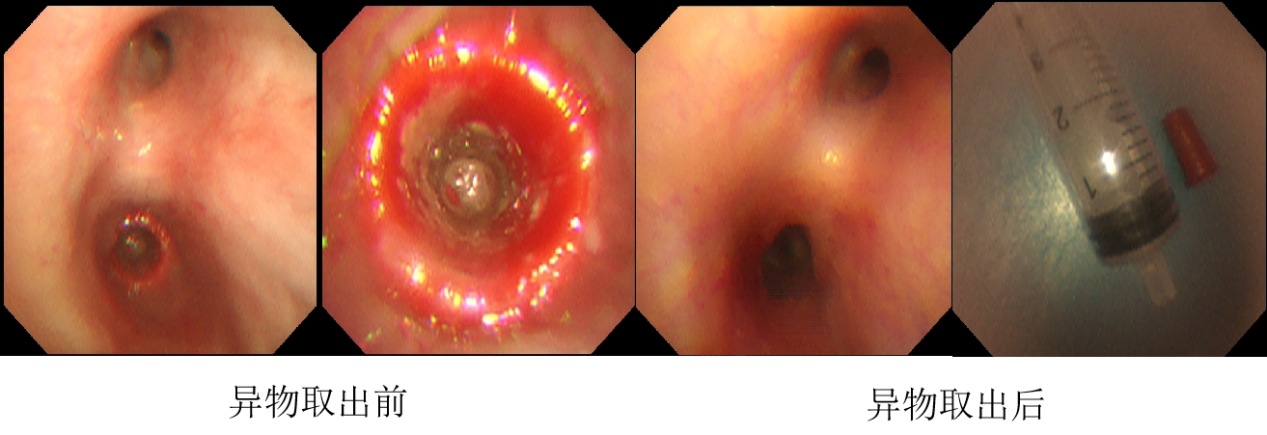

由于异物嵌顿时间长,已有七月之久,住院后患者受到科室的重视,儿科主任杨琳教授看过患儿后指示做好万全准备,制作两套计划,先行支气管镜探查,取异物,若未成功,再联合耳鼻喉科进行硬支气管镜下取异物。王慧渊主治医师、申丹丹住院医师和谢梅副主任护师的默契配合下,凭借着精湛的技术,通过儿童支气管镜精准定位到异物所在位置,并成功将其取出,让孩子转危为安。

异物取出后,患儿安返病房,经过7天充分抗感染治疗,复查胸部CT示右中间段支气管通畅,右肺下叶炎症明显吸收,好转出院。